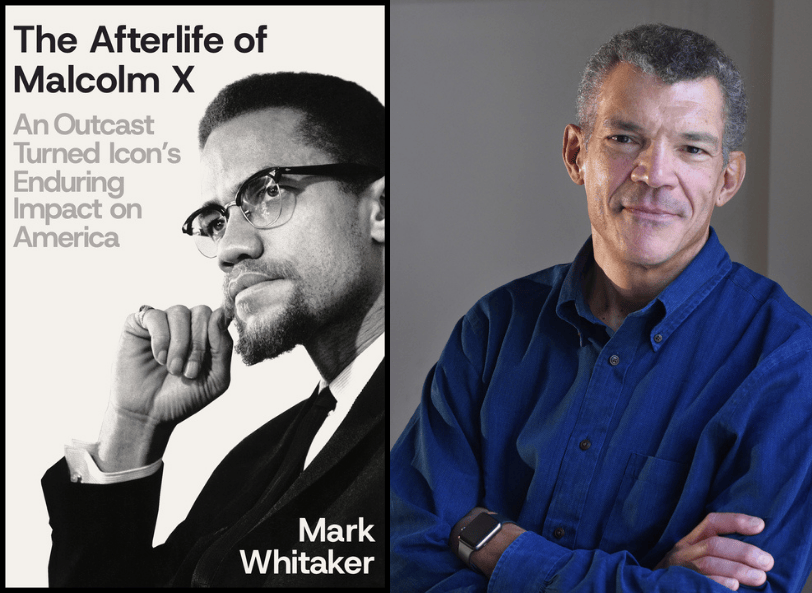

Katherine Koh.

Niles Singer/Harvard Staff Photographer

Katherine Koh, assistant professor of psychiatry at Harvard Medical School and a psychiatrist at Massachusetts General Hospital and its partner Boston Health Care for the Homeless Program, penned a recent article in the journal JAMA Internal Medicine highlighting the approach’s success at improving access and reducing barriers to care.

In this edited conversation with the Gazette, Koh said she’s seen the effect in her own practice, and she and co-authors from MGH, BHCHP, Boston Medical Center, and Brown University want to continue research on this approach and highlight its success for others assisting this hard-to-reach population.